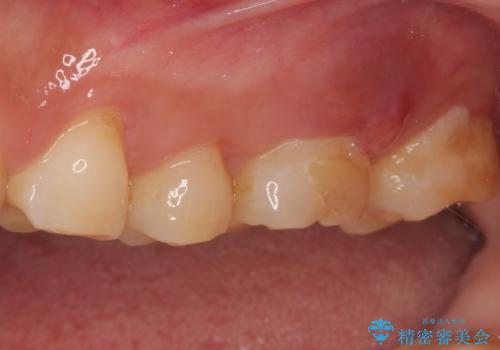

- 奥歯で咬んだときに痛みがあり、膿の出口が現れたとのことで来院された患者様です。

かかりつけ医では治療が困難と言われたとのことで当院にいらっしゃいました。

診査を行った結果、まずは根管治療を行うこととしました。

咬み合わせが非常に強く、臼歯のみに咬合力が集中している咬み合わせだったので、根管治療後はPGAクラウン(白金加金合金クラウン)にて補綴する治療計画となりました。